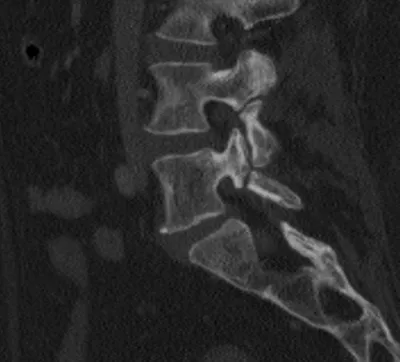

Pars Interarticularis Radiology Images

Browse 2 medical images tagged with pars interarticularis. This collection includes various imaging modalities for medical education and reference.

This collection contains 2 radiology images related to pars interarticularis, including various imaging modalities such as X-rays, MRIs, CT scans, and ultrasound images commonly used in medical diagnosis and education.